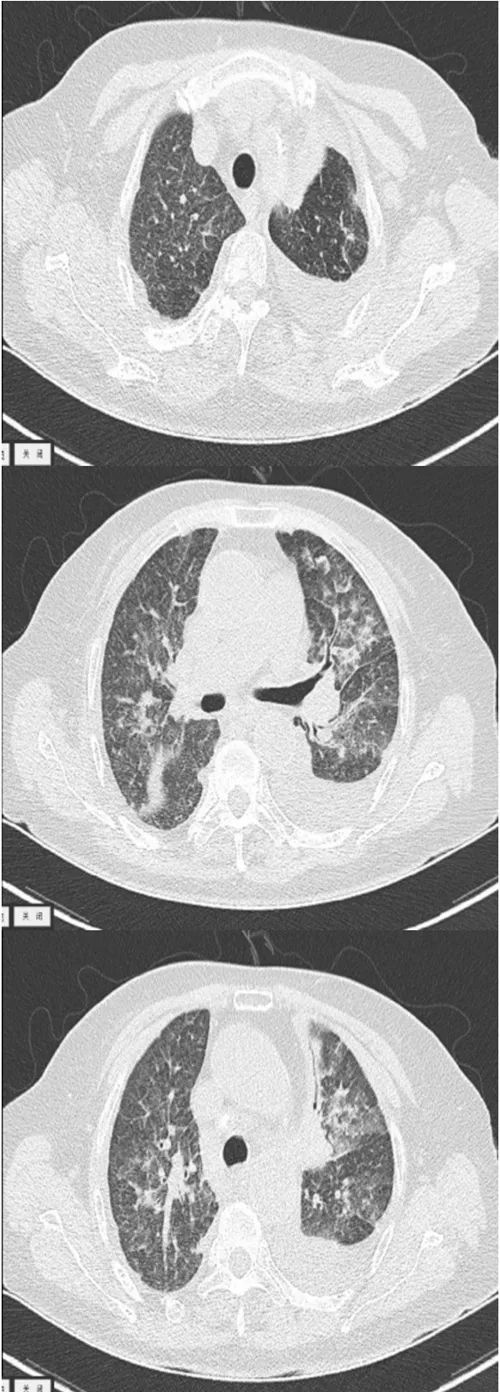

但患者11月12日再次出现发热。复查肺部CT显示:两肺散在多发炎症,两侧胸腔少量积液伴邻近肺组织膨胀不全,双侧支气管壁增厚,部分管腔狭窄,纵隔多发淋巴结(图4)。

图4 复查肺部CT